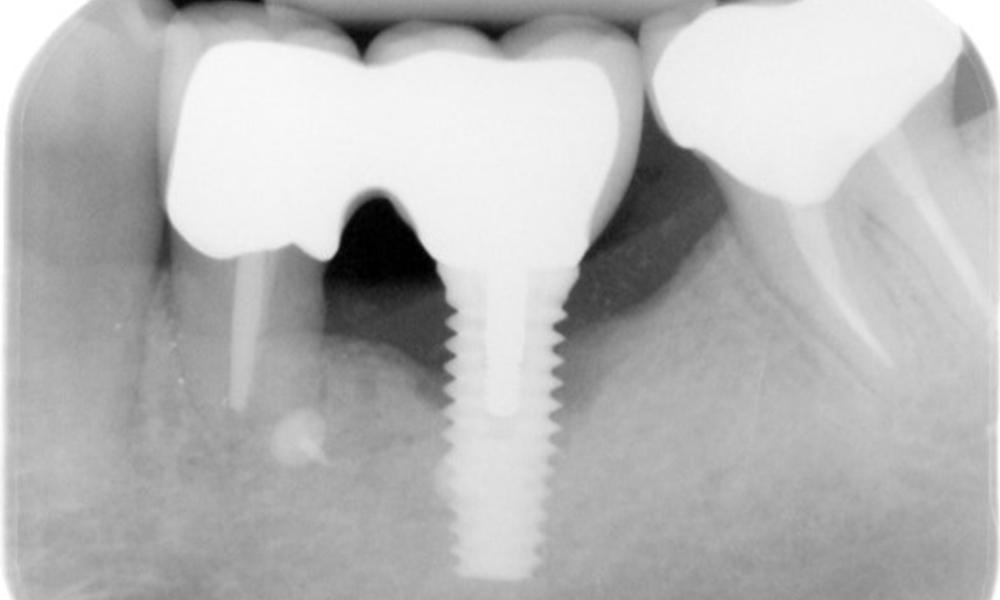

The X-ray images show the progression of bone loss.

The X-ray images show the progression of bone loss in the area of the implant in region 36: dental film from 11.02.2021 (left) and dental film from 18.01.2024 (right).

OPG: 26/02/2024 Dental X-ray: 18/01/2024